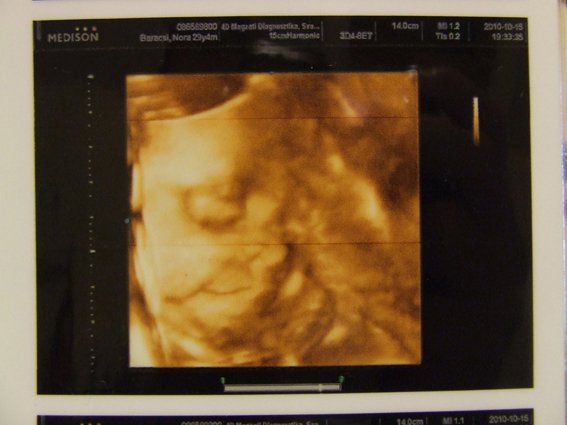

Bocsi, most kicsit rövid és önző leszek, most megyünk 4D-re!!! :)

Majd jövök fotókkal és olvasgatok is majd, mert úgy látom elég sok minden volt megint.